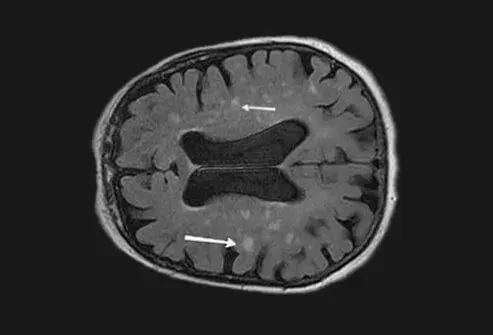

Billede af vaskulær (multi-infarkt) demens 1

Picture of Vascular (Multi-Infarct) Dementia

Billedkilde: Alzheimers sygdomsuddannelse og henvisning Center National Institute on Aging